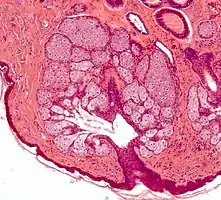

Multiples glandes sébacés volumineuses réalisant une hyperplasie sébacée.

- L'hyperplasie sébacée (voir Sebaceous hyperplasia (en)), se référant à une prolifération excessive des cellules dans les glandes, et visible macroscopiquement sous forme de petites papules sur la peau, particulièrement sur le front, le nez et les joues[28].